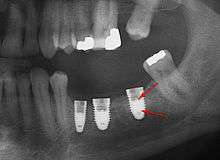

These are usually called prosthetic implant abutments. These abutments can be made from a variety of materials, such as titanium, surgical stainless steel and gold. More modern abutments are now also made from zirconia,[3] which is a white ceramic, to better complement the aesthetics of a dental implant restoration. The two images to the right show a ceramic abutment and the ceramic crown bonded to it. The images to the right show how a ceramic abutment can enhance a ceramic crown by giving it a more lifelike appearance. Ceramic abutments have to be used with care, however, since their compressive strength is nowhere near that of titanium, gold or other noble metals. Most clinicians feel more comfortable using a metal prosthetic abutment in the posterior molar areas, due to the increased masticatory forces present in these areas.

An abutment is not necessarily parallel to the long axis of the implant. It is utilized when the implant is at a different inclination in relation to the proposed prosthesis. Most crowns and fixed partial dentures have a cemented or screw-retained fixation on the abutment.

In a three piece implant the abutment is fixed on the implant with a screw butt joint.[4] This screw needs to be tightened to a predetermined torque with a dental torque wrench, in order to avoid screw loosening during chewing, which can often create a counter-clockwise torque on the implant-abutment interface, encouraging the abutment screw to come loose. This can largely be prevented with proper screw design and torquing of the abutment.

In a two piece implant the abutment is morse tapered or cold welded on the implant. Microbial leakage and colonization between the implant and the abutments can result in inflammatory reactions and crestal bone loss. Morse taper conical abutments showed a cumulative implant survival rate of 98.23%[5] in terms of seal performance, microgap formation, torque maintenance, and abutment stability.[6]